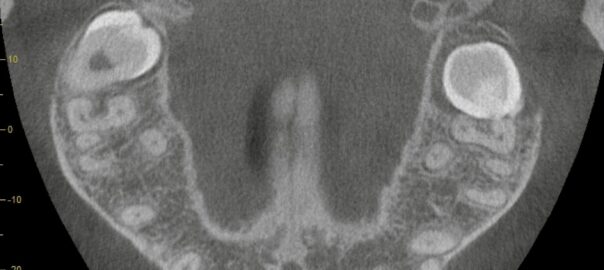

【下歯槽神経に近接した深部埋伏親知らず】左右4本すべて完全埋伏|CT精査の重要性と麻痺リスクを最小限にする抜歯戦略

こんにちは。東京都中央区銀座5丁目にある 【親知らず・顎関節症クリニック銀座(通称:オヤアゴクリニック)】です。 当院は以下の3つに特化した歯科クリニックです。 * 親知らずの抜歯 * 顎関節症の治療 * アスリートのた … 続きを読む 【下歯槽神経に近接した深部埋伏親知らず】左右4本すべて完全埋伏|CT精査の重要性と麻痺リスクを最小限にする抜歯戦略